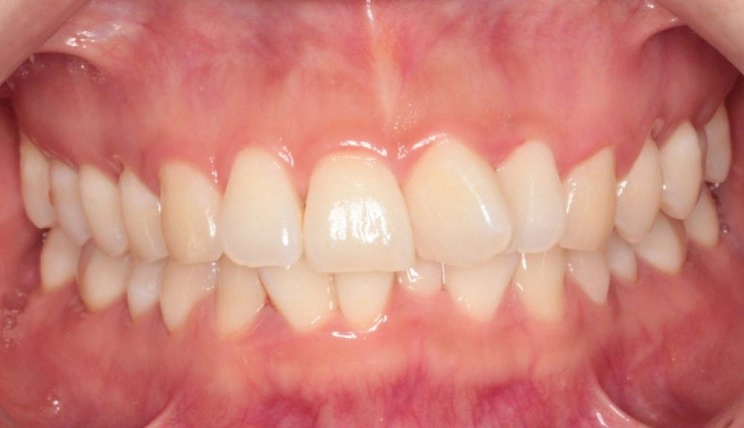

Crowding

Crowding is the condition in which there is a discrepancy between tooth size and space available for the teeth to be aligned in the dental arch

Patient Information:

Age: 17

Gender: female

Invisalign Treatment Option: Invisalign Comprehensive

Total Treatment Time:

29 months